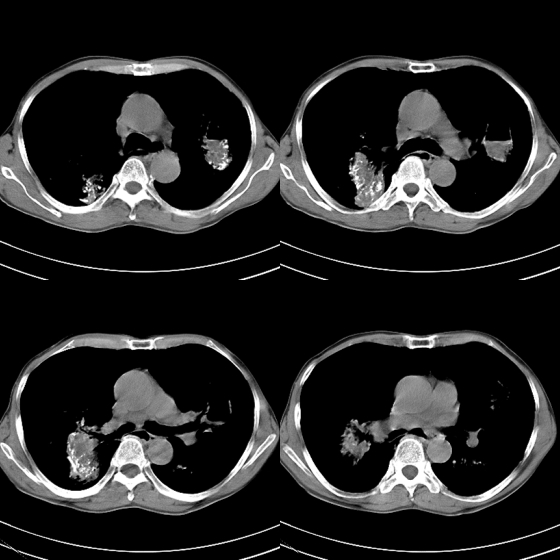

标题: CT21797:M65y,矽肺团块内空洞?

m65y,咳嗽、咯痰,煤工工作史10+年。低热,无明显脓臭痰。临床怀疑tb。

我也明知故犯一次!1、矽肺伴结核, 右下病变不排除瘢痕癌;2、慢支、肺气肿、多发肺大泡并气胸。

煤工尘肺结节易液化坏死,形成空洞,如合并结核形成空洞,周围应该有播散灶。

矽肺伴结核(左肺上叶病灶内空洞形成),右侧气胸,两肺多发性肺大泡。

、矽肺伴结核同时合并感染, 右下病变不排除瘢痕癌;2、慢支、肺气肿、多发肺大泡并气胸。

告病重没有?这种气胸不易复张,咳嗽剧烈左肺大泡再破就难活了。煤尘肺常继发结核,影像学不易鉴别。有结核的可疑临床症状,ppd5u皮试阳性,特别是强阳性,就有诊断性抗痨治疗指针。不过排他性诊断是最重要的。左上空洞内液平就不是结核应有的。同意9楼楼主看法,同时注意合并感染的问题,抗炎覆盖广一点。